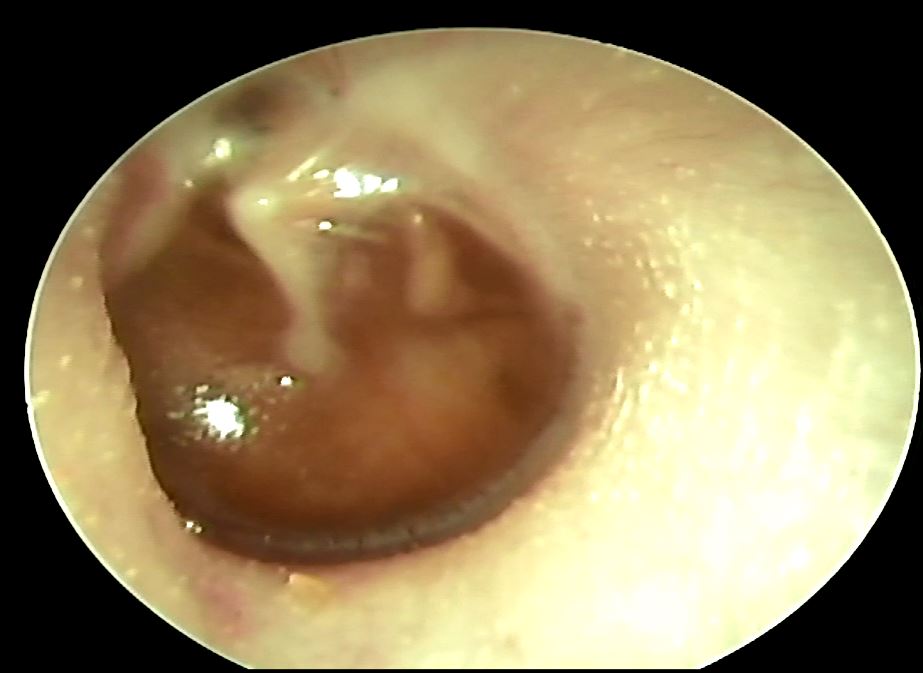

中耳腔藉由耳咽管平衡裡面的壓力,如果耳咽管本身阻塞或是呼吸道的纖毛運動變差,原本裡面的黏液就排不出來,久了就會形成積水狀,積水一多就有可能會造成耳鳴、耳悶、聽力減退等等現象;中耳腔積水又稱為glue ear,意思就是裡面可能會有清澈的或是黏稠的液體,孩子一般會有輕度聽力減退 (大約會掉27分貝) 或是語言發展遲滯等現象,跟急性中耳炎不一樣的地方是一般不會有耳痛、發燒或是倦怠等症狀。

中耳腔積水占所有小孩的中耳炎的25-35%,中耳腔積水一般好發在4歲以前的兒童身上,跟本身耳咽管還沒發育完全有關,超過6歲就比較少發生,美國跟歐洲的研究顯示大約有5成到8成的小孩四歲前曾經發生過中耳積水,危險因子有 : 六歲以下、在托育中心待過、很多兄弟姊妹、常常感冒、瓶餵牛奶以及家裡有人抽菸,積水的話可能以後比較容易出現耳膜穿孔、鼓室硬化症、耳漏、膽脂瘤等等問題;積水的話不見得會發燒也不見得積水裡面就會有細菌滋生,所以抗生素的使用其實在醫界是有爭議的,至於抗組織胺、去充血劑以及鼻內類固醇也是沒有一個定論。

如果在一個上呼吸道感染之後發現有中耳積水的情形,通常會建議觀察3個月左右,如果積水沒有消退再考慮置放中耳通氣管引流,以免時間太久影響聽力造成學習上的問題,在英國中耳腔積水是幼童轉診做手術最常見的原因,研究指出如果單純只放管子可能效果沒那麼夠,建議要搭配鼻內的腺樣體切除手術會比較好,至於媽媽們常常問說可不可以游泳,耳膜如果沒有置放通氣管的情況下,游泳或是洗澡都不會有問題的,但是如果置放了中耳通氣管可能就要避免進水以免中耳炎,另外,如果是發生在成人身上,就要考慮是不是鼻咽有長腫瘤,一般耳鼻喉科醫師會做個鼻咽內視鏡確認一下,所以如果長期有耳悶、耳鳴或是聽力喪失的情況,請至耳鼻喉專科門診檢查以免延誤治療!!